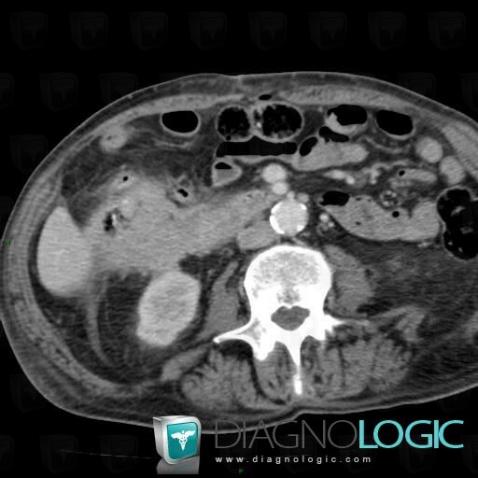

Colon cancer, Duodenum, CT

Here is the specific information in the key image above:

- Diagnosis Colon cancer, Location(s) Duodenum, with gamuts